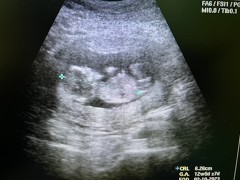

น้องได้12wคะ ลุงหมอบอกเซิ้งเป็นแล้ว